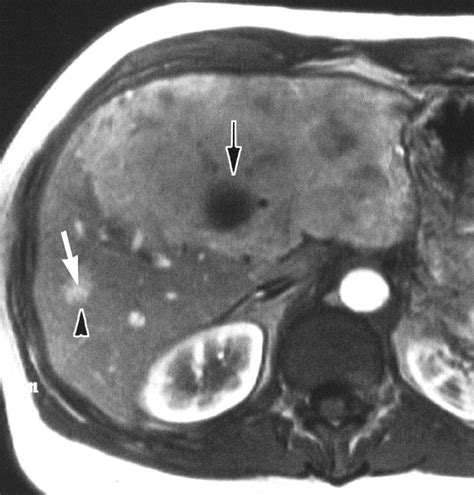

Distinguishing a benign nodular hyperplasia liver lesion from a malignant tumor requires precise diagnostic imaging. Because the texture of the growth is different from surrounding healthy liver tissue, radiologists use specific protocols to identify the classic “scar” often associated with FNH. The goal of the medical team is to avoid invasive procedures like biopsies whenever possible.

Contrast-Enhanced MRI The gold standard for identifying the central scar and blood flow patterns.

CT Scan Useful for visualizing the nodule’s shape and its relationship to nearby vessels.